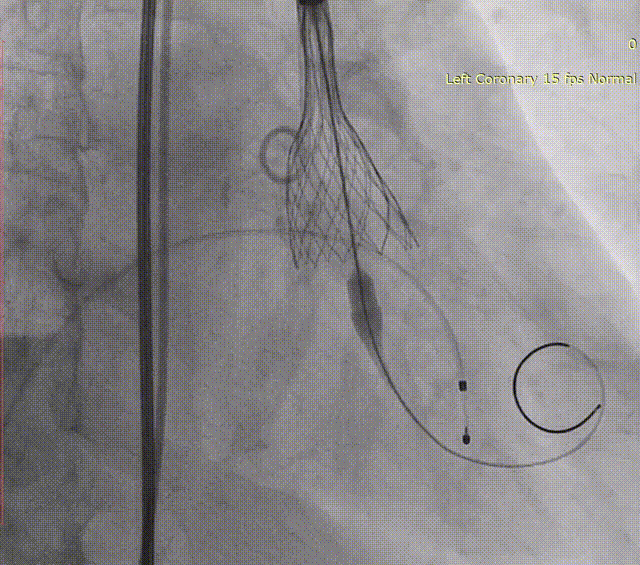

TAVR手术过程

主动脉根部造影

球囊预扩

瓣膜释放

完全释放后造影